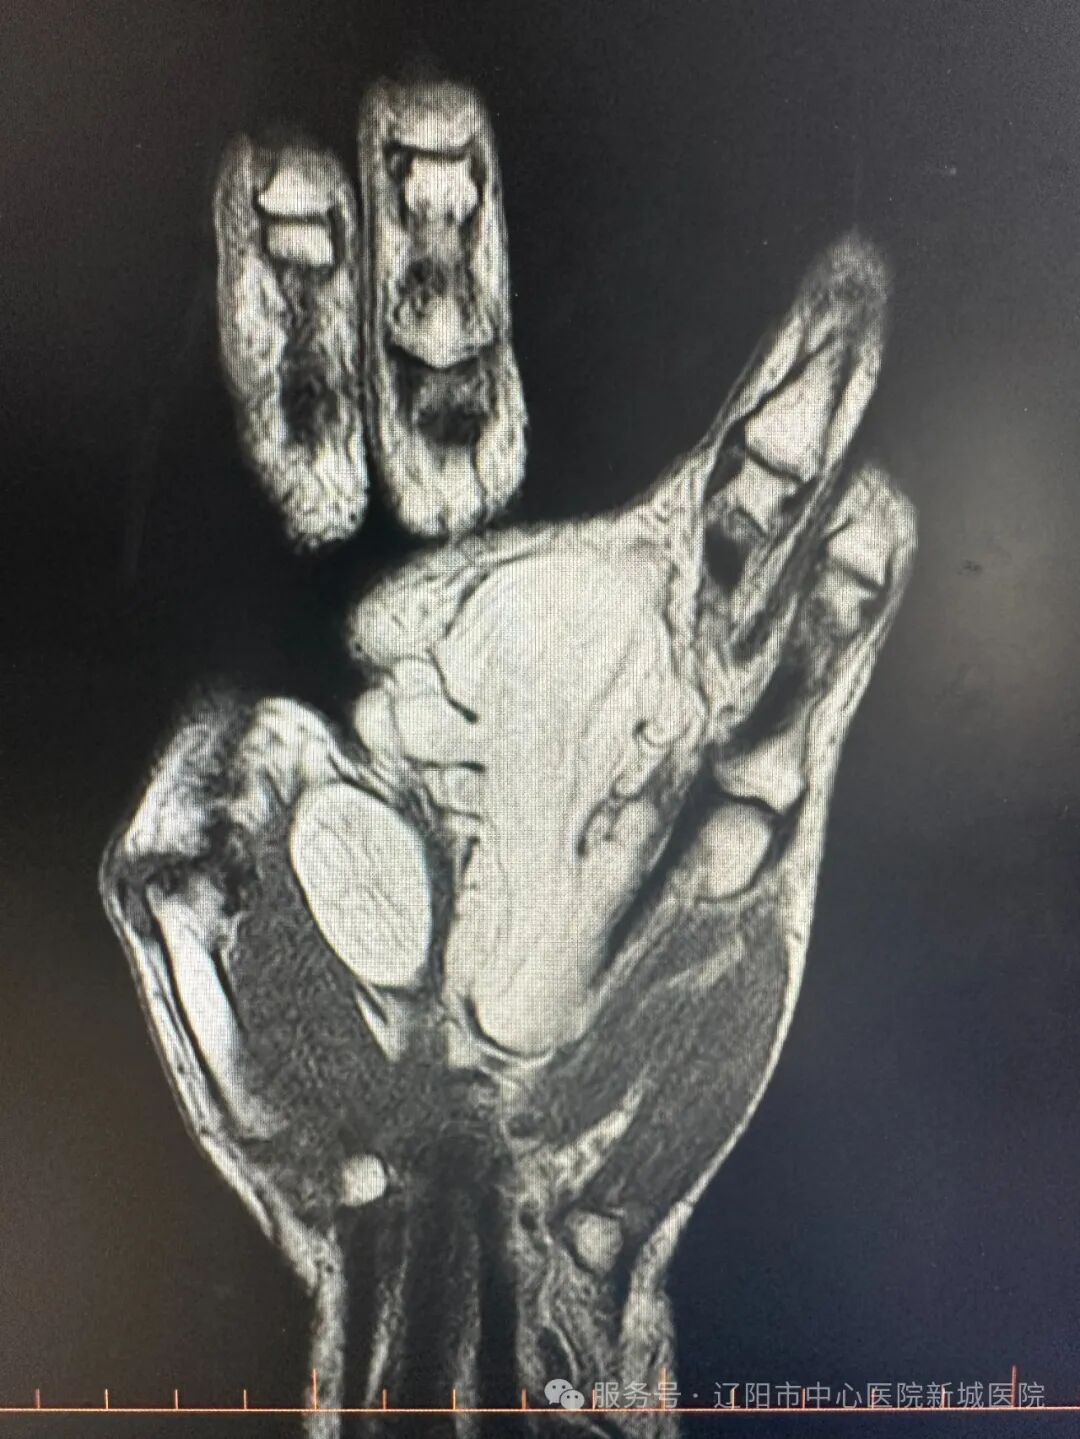

骨科副主任姚克勝接診,通過(guò)查體和影像學(xué)檢查,于先生被確診為:左手腫物,左手掌及第3.4指根部長(zhǎng)有4.7×7.1厘米腫物,建議手術(shù)治療。

于先生入院第二日,姚主任帶領(lǐng)醫(yī)療團(tuán)隊(duì)為他進(jìn)行肌間腫物切除術(shù)。術(shù)中可見:腫物被膜完整,成放射性生長(zhǎng),與掌筋膜黏連嚴(yán)重,壓迫了指神經(jīng)。按照既定的手術(shù)方案,姚主任與團(tuán)隊(duì)人員精心細(xì)致的將腫物與神經(jīng)、血管、肌腱進(jìn)行解剖剝離,保護(hù)神經(jīng)、血管、肌腱不損傷,恢復(fù)了手部的外型美觀。